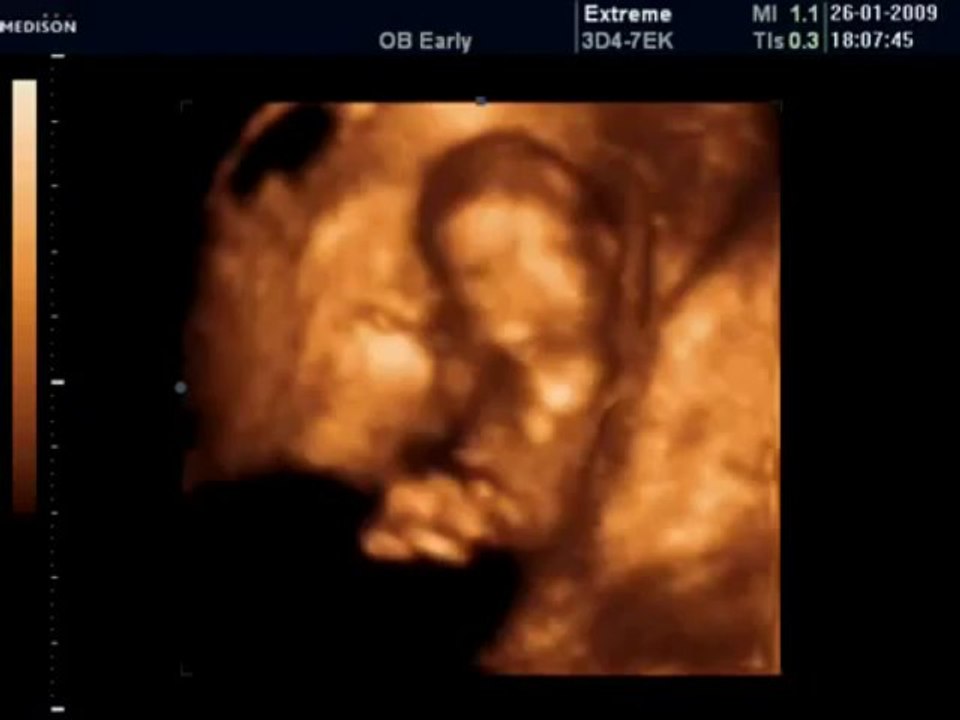

26 Haftalık Gebelik Bebek Ultrason Görüntüsü Dailymotion Video

26 haftalık olmuş bir bebek yavaş yavaş büyümektedir. 26 haftalık gebelikte ultrason yoluyla bebeğin her şeyini rahat görebiliriz. Bir yandan kilo alan bebeğin bir yandan.

26 haftalık gebelikte ultrason yoluyla bebeğin her şeyini rahat görebiliriz. Gebelik haftasının sonunda bebeğiniz yaklaşık 900 gr kadardır. Hamilelik 40 hafta üzerinden hesaplanır.